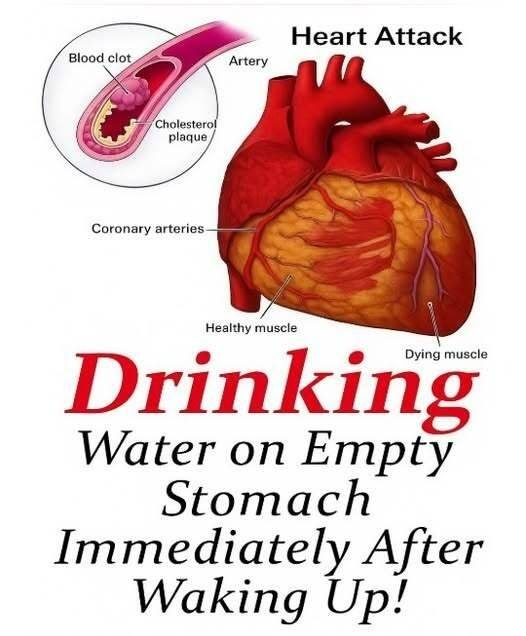

Did you know that drinking water on an empty stomach could be…

Starting your day with a glass of water is one of the simplest health habits—and one of the most often recommended. But is drinking water on an empty stomach truly special, or is it just another wellness trend? Let’s break down what science really says. Why Water Matters Water makes up about 60% of your body and … Read more